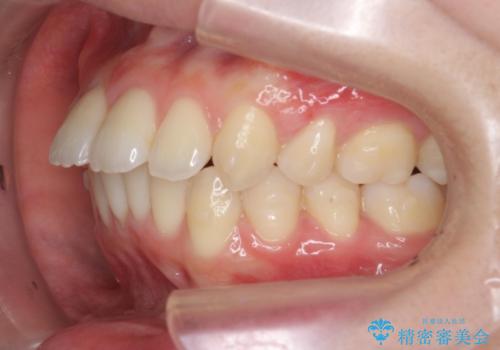

突き出た前歯の改善!マウスピースで再矯正

- 5年前にワイヤー矯正治療を終了したが、突き出たように見える前歯の仕上がりが気に入らず、再矯正治療を希望され来院されました。

マイクロインプラントを用いた遠心移動とIPRを行うことによる前歯の突出感の改善をマウスピース矯正治療で計画します。

突出していた前歯の角度が大きく改善し、審美的な仕上がりに満足いただくことができました。